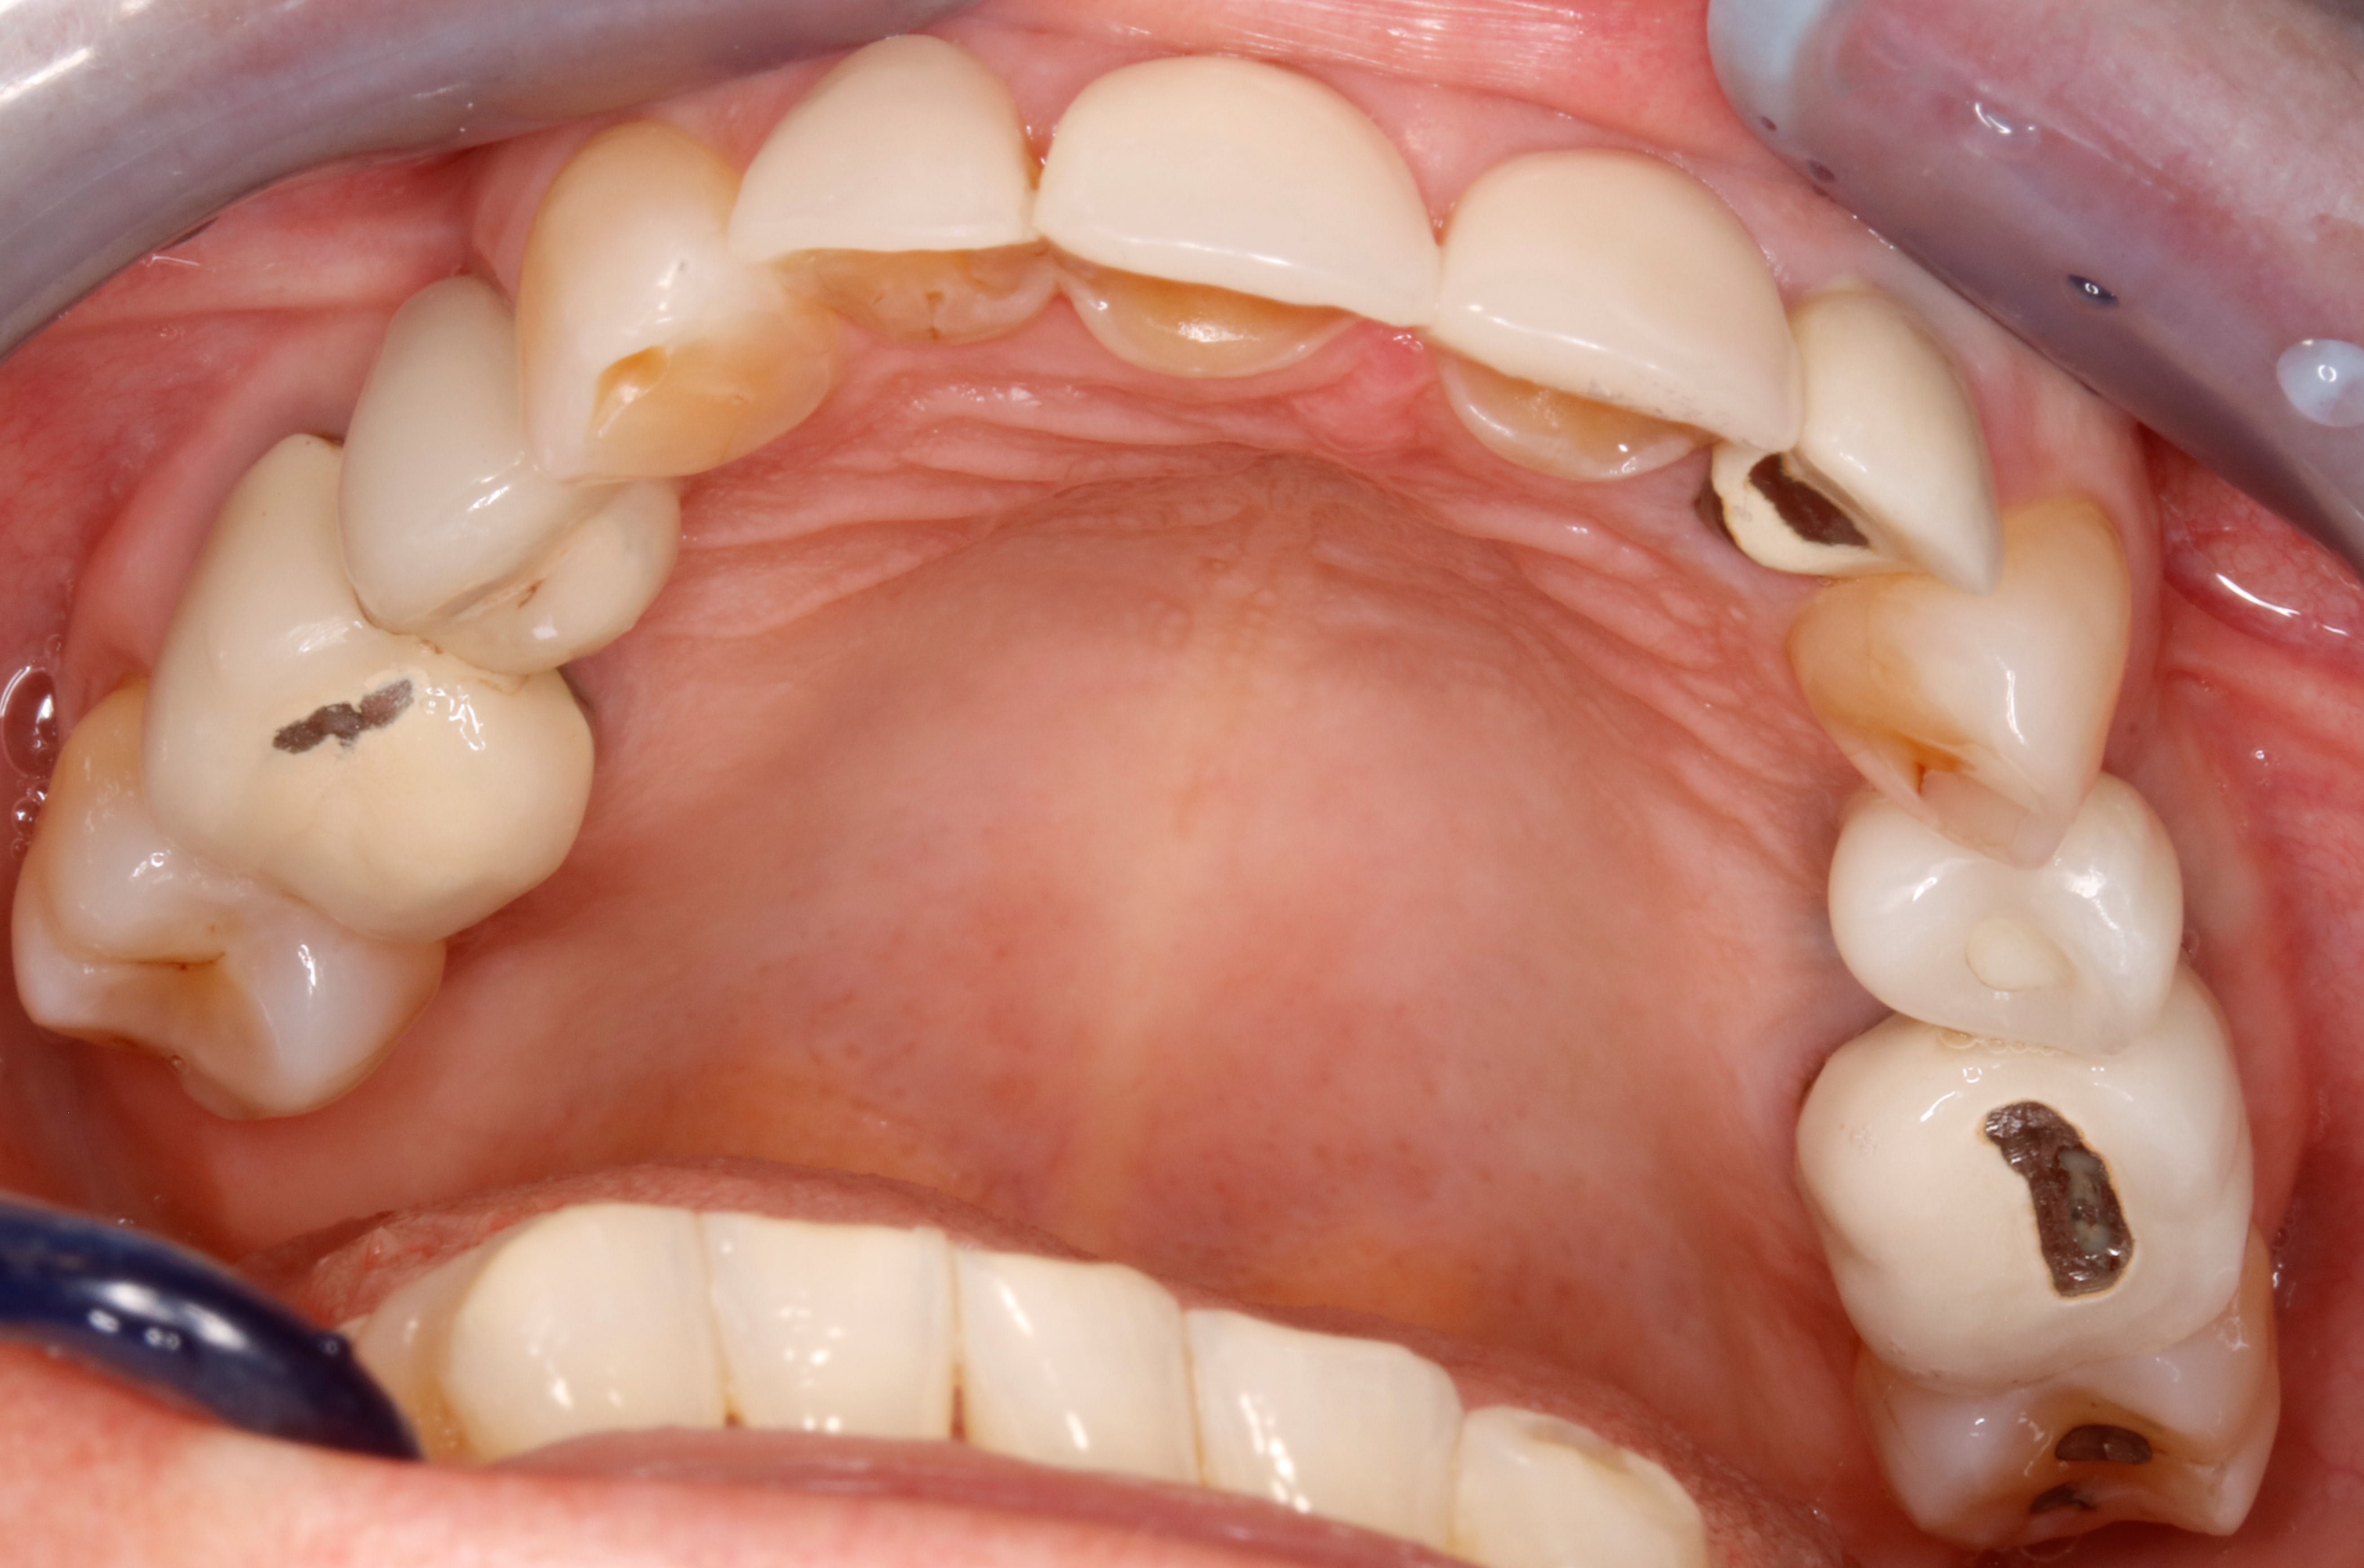

obligé de couper la photo , pcq je l ai trop grosse soit disant

photo inversée par le miroir

Ben , elle penche à droite mais use à gauche ....34 35 usées , 24 implant pcq la 24 a lachée . Pourquoi ? ben j'en sais rien . Elle a la tronche en biais ?

Pourquoi on lui a volé des PM sup ?

Elle penche à droite car il manque la 42

Les prémo inf sont trop lingualées,

Le calage post est merdique en particulier secteurs 2 et 3 donc 26/27 et 36/37

Ça forme une marche quelle veut virer donc mode meule avant arrière sur ce côté et dans le mouvement la 12 dégage

Bilan, tu refais comme il faut ces 4 couronnes pour remettre comme il faut les courbes et le problème est grandement géré

j y vois une supraclusion , de l usure , un passif orthodontique par l absence de PM , une asymétrie des incisives du bas , un sur guidage ant , bref que cette occlusion d aujourd'hui , n est certainement pas celle d'hier et qu il y a bien eu une dérive latérale .

ce qui ne m arrange pas , pcq je n ai pas de place pour faire une couronne sur 12 , la facette n étant plus possible .